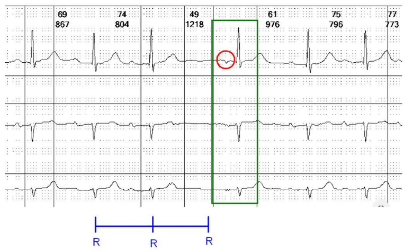

A diferença em relação à extrassístole é que o escape é sempre um batimento tardio

Em outras palavras, enquanto a extrassístole é um batimento precoce em relação ao ciclo de batimentos anterior, o escape é tardio, isto é, vem após o momento em que seria esperado o batimento normal. Isso acontece porque o escape é um batimento de suplência: Ele evita que o coração fique sem bater por longos períodos e, assim, uma parada cardíaca.

Por isso, temos desde escape atrial, passando pelo juncional até o ventricular. Quanto mais distante do nó sinusal, maior vai ser a pausa que precede o batimento de escape.

Exemplo de escape Juncional